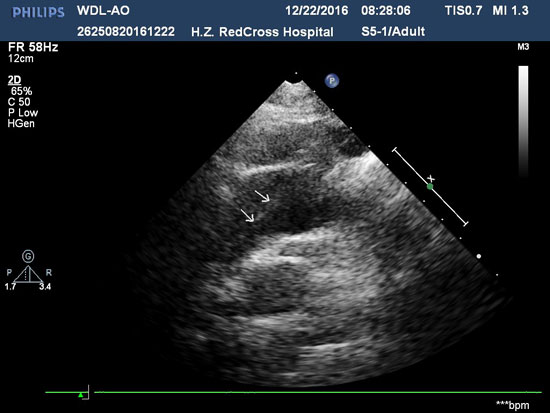

随后,超声医学科王大力副主任医师检查到病人的腹部大动脉位置上时,凭借多年的临床经验,立马发现了张先生的病情“不一般”!超声波显示,腹主动脉内一根条带在来回飘动,他的腹主动脉“分层了”!危险!王大力医生立马对张先生的心脏进行了检查,发现主动脉弓内也存在这样的条带,这是人体内最危险的疾病之一“主动脉夹层”!

患者心脏主动脉弓内的血管夹层

经放射科CTA检查,确诊为主动脉夹层DeBakey I型,血管外科金弢主任医师为张先生迅速制定手术方案,凭借娴熟的技术和丰富的经验,顺利完成手术。“多亏你们及时的发现,才让我有惊无险!”张先生术后恢复良好,没多久就出院回家静养了。